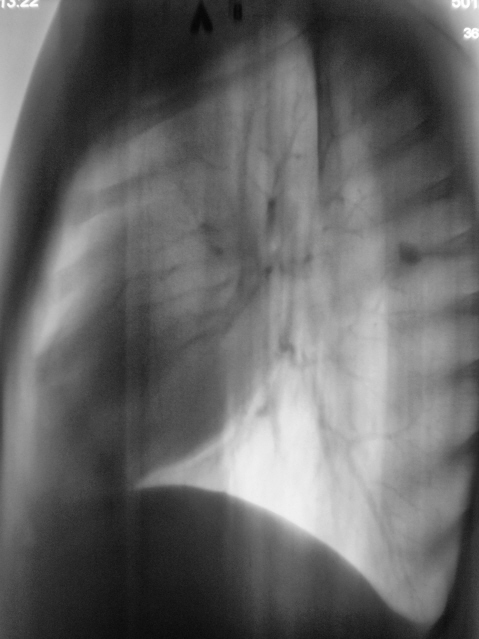

101.Rasshifrovka.JPG

Кстати, а такое образование ещё может соответствовать сосудистой мальформации, другое дело, что если раньше этого небыло. А если сравнивать от 2008г. так без динамики.

Добавлены данные за 2007 год.

Валентин Львович, а тень справа на уровне ключицы и переднего отрезка I ребра (лучше всего видно на снимке за 2007г. - он с небольшим поворотом) это меня глючит?

Я не думаю, что Вас "глючит", так как Вас просто "не может глючить". Я тогда, в 2007 году, "повязал" скиалогическую картину справа на уровне 1 ребра справа, и наличие овальной формы тени средней интенсивности слева в 3 межреберье. Один из наших уважаемых пользователей, сказал как-то, что я "постоянно заточен на туберкулёз", и это правильно, с учетом "нашей эпидситуации". Так вот тогда, я с большим скрипом и неудовольствием, высказался в пользу специфического процесса, хорошо понимая, что данных весьма мало.